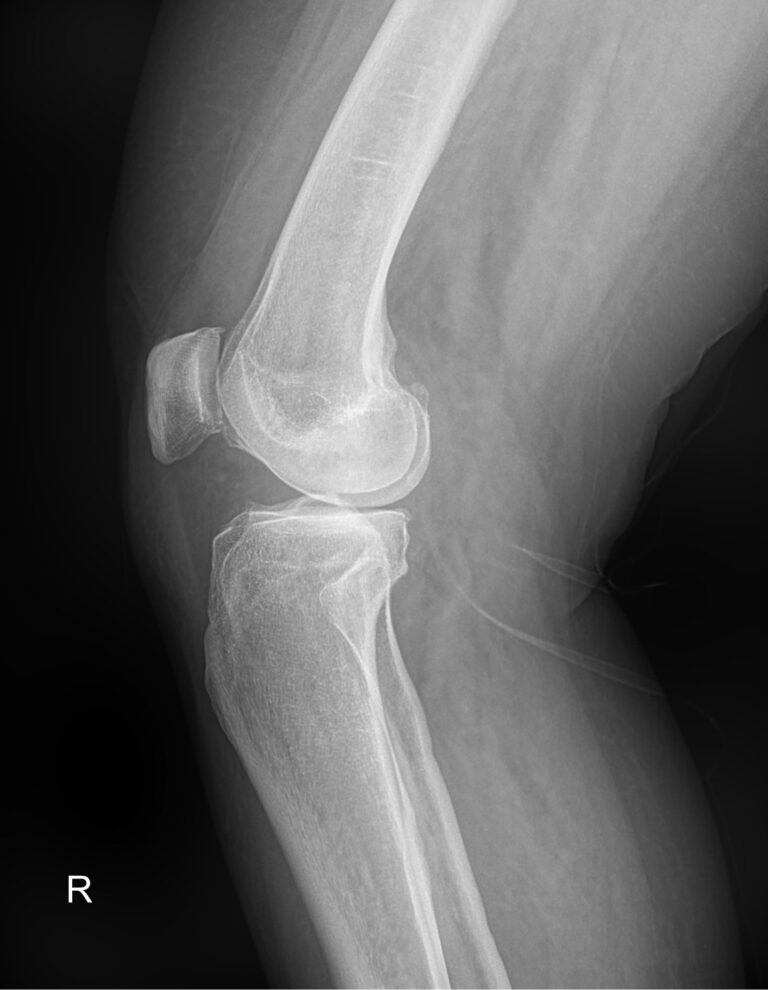

Рентген ― самый простой и быстрый метод диагностики поражения коленных суставов. Это неинвазивный и безболезненный , а также высокоинформативный способ увидеть внутреннее состояние колена. Современное рентгеновское оборудование использует минимально возможную дозу облучения. При этом на рентгенограмме отчетливо просматриваются части бедренной, малоберцовой и большеберцовой костей, надколенник, а также мягкие ткани вокруг них.

На рентгенограмме будут видны элементы сустава и патологические изменения в них:

• Суставная щель ― может быть расширена или сужена, причем неравномерно, иметь выпот, выросты, костные и хрящевые обломки;

• Соответствие друг другу суставных поверхностей ― естественное или вывих;

• Положение надколенника ― может быть неестественным;

• Состояние костной ткани: перелом, разрежение, уплотнение, размягчение, склерозирование;

• Мягкие ткани ― нормальные или отекшие, с инородными телами.

Подготовки не требуется. Пациент снимает одежду ниже пояса кроме белья и ложится на снимочный стол. Для прямой или передне-задней проекции ноги надо вытянуть. Рентгенолаборант накрывает туловище защитной накидкой. Необходимо замереть на 2 секунды, пока происходит съемка.

Рентгенограмма в другой проекции, назначенной лечащим врачом, требует положения на боку, при котором больную ногу слегка сгибают, а здоровую отводят немного назад.